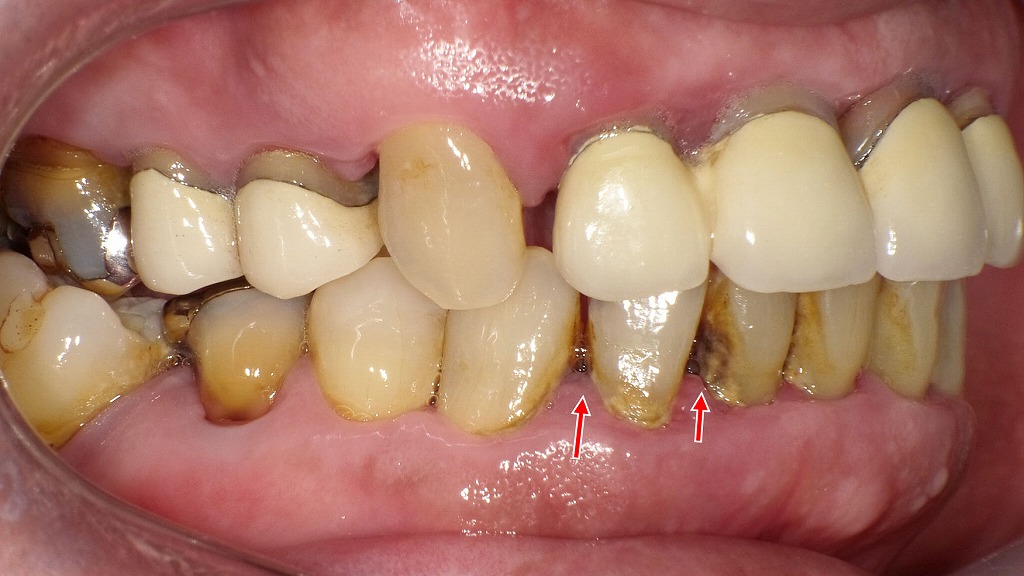

歯周病・虫歯予防のサポートに|マウスウォッシュの役割

歯と歯ぐきの境目に付着したプラークや歯石は、歯周病や虫歯の大きな原因になります。マウスウォッシュは、ブラッシングだけでは届きにくい部位の細菌数を減らし、歯周病予防・虫歯予防を補助する役割があります。ただし、マウスウォッシュだけで汚れを落とすことはできないため、毎日の歯磨きと歯科医院での定期的なクリーニングを基本とし、補助的に取り入れることが大切です。